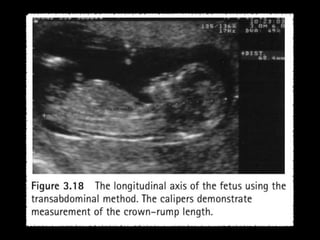

CRL

Accuracy of dating- When biological variability is

minimal:

CRL is more accurate than BPD

But can be the most difficult measurement to

obtain

Dependant on operator